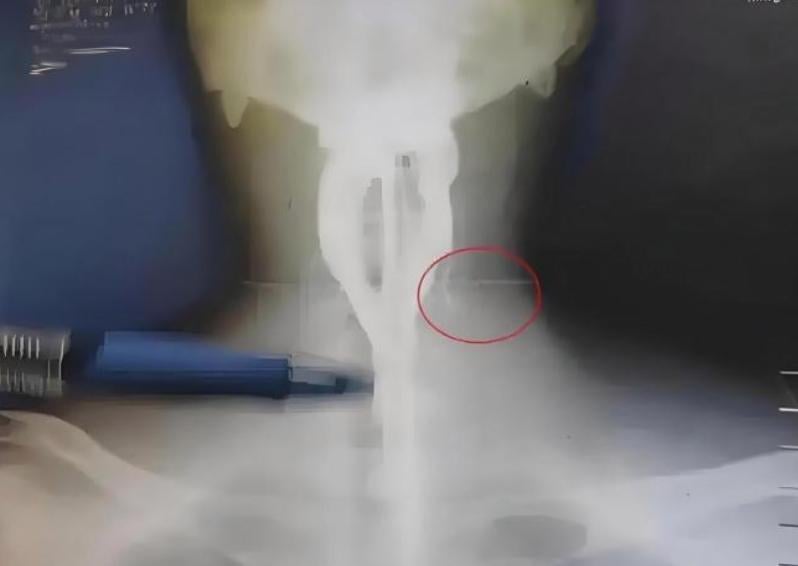

男子脖子腫痛,X光顯示內有異物。(圖/翻攝環球網)

據官方《環球網》報道,深圳市人民醫院通報,這名程式設計師阿偉(化名)因頸部出現腫塊,且壓迫到耳神經造成劇烈疼痛而就醫。醫生初步以抗生素治療,但膿腫消退情況不理想,隨後進行排膿手術。在手術過程中,醫師意外發現膿液中存在黑色異物,經病理化驗確認為7粒瓜子。